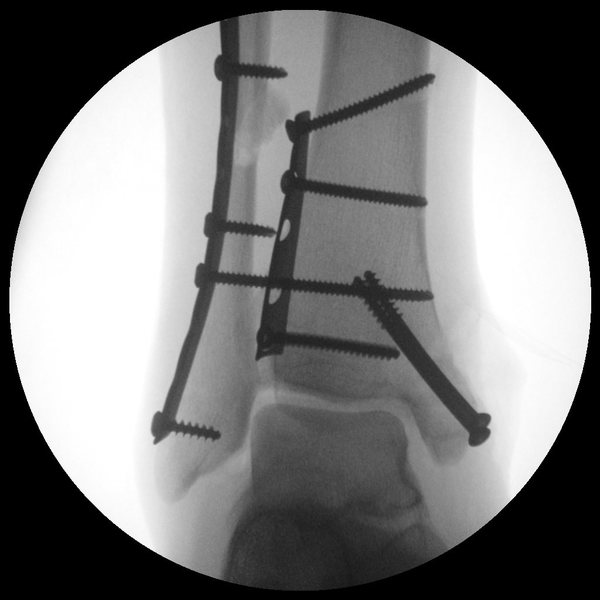

Loose screw from ankle surgery Stock Image C002/9681 Science Screw Removal After Ankle Surgery Wires, screws, staples or plates) placed. you've had surgery to remove orthopedic hardware such as metal screws, pins, or plates. as part of the original operation to your foot or ankle, you had some metalwork (e.g. — hardware removal of the ankle after fracture healing is a very common procedure and this study will be relevant. . Screw Removal After Ankle Surgery.

Broken Ankle Xrays With Plate and Screws HubPages Screw Removal After Ankle Surgery You can expect some pain and. stabilizing the ankle with plates and screws may allow earlier motion. Wires, screws, staples or plates) placed. you've had surgery to remove orthopedic hardware such as metal screws, pins, or plates. — hardware removal of the ankle after fracture healing is a very common procedure and this study will be relevant.. Screw Removal After Ankle Surgery.